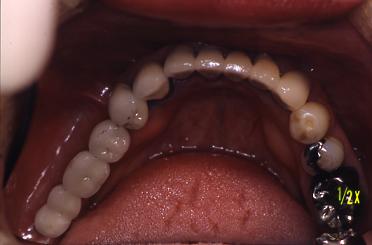

【症例 2】右下奥歯3本欠損 (64才,女性)

術前

右下奥歯3本の歯がないです